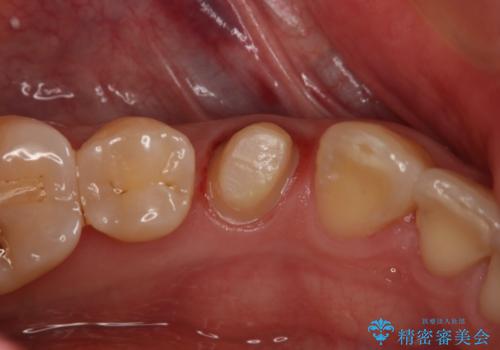

- 左下4番のう蝕を指摘され治療を希望された患者様です。

切削量などを考慮しクラウンでの治療を提案したところ、セラミックを希望されたのでフルジルコニアクラウンでの治療を選択しました。

う蝕が深かったので痛みが出る可能性をお伝えしましたが特に症状は現れなかったので、予定通りセラミッククラウンでの治療を行いました。